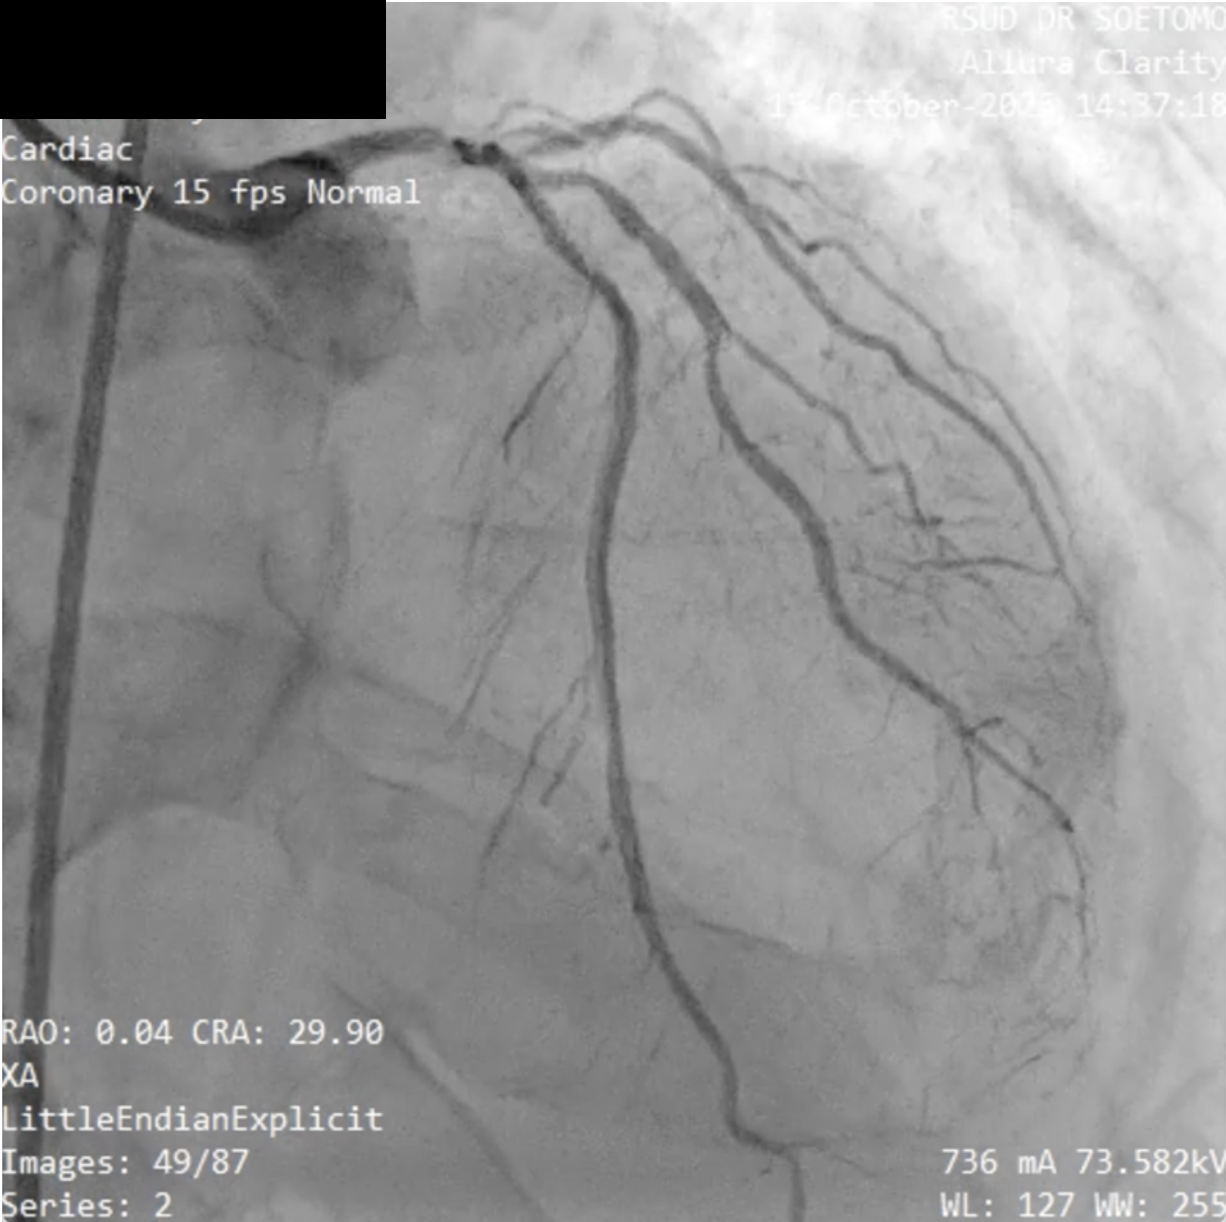

Relevant Catheterization Findings

Diagnostic coronary angiography revealed a right-dominant coronary circulation with 80% distal left main stenosis involving the LAD, LCx, and Ramus Intermedius (Medina 1-1-1-1 true trifurcation). The LAD showed 90% ostial-proximal stenosis, the LCx 90% ostial stenosis, and the RI 90% proximal stenosis. There was a non-significant 40% stenosis at the mid-distal RCA with extensive collateral flow to the distal LCx, LAD, and septal branches via the conus branch, RPLB, and RPDA.